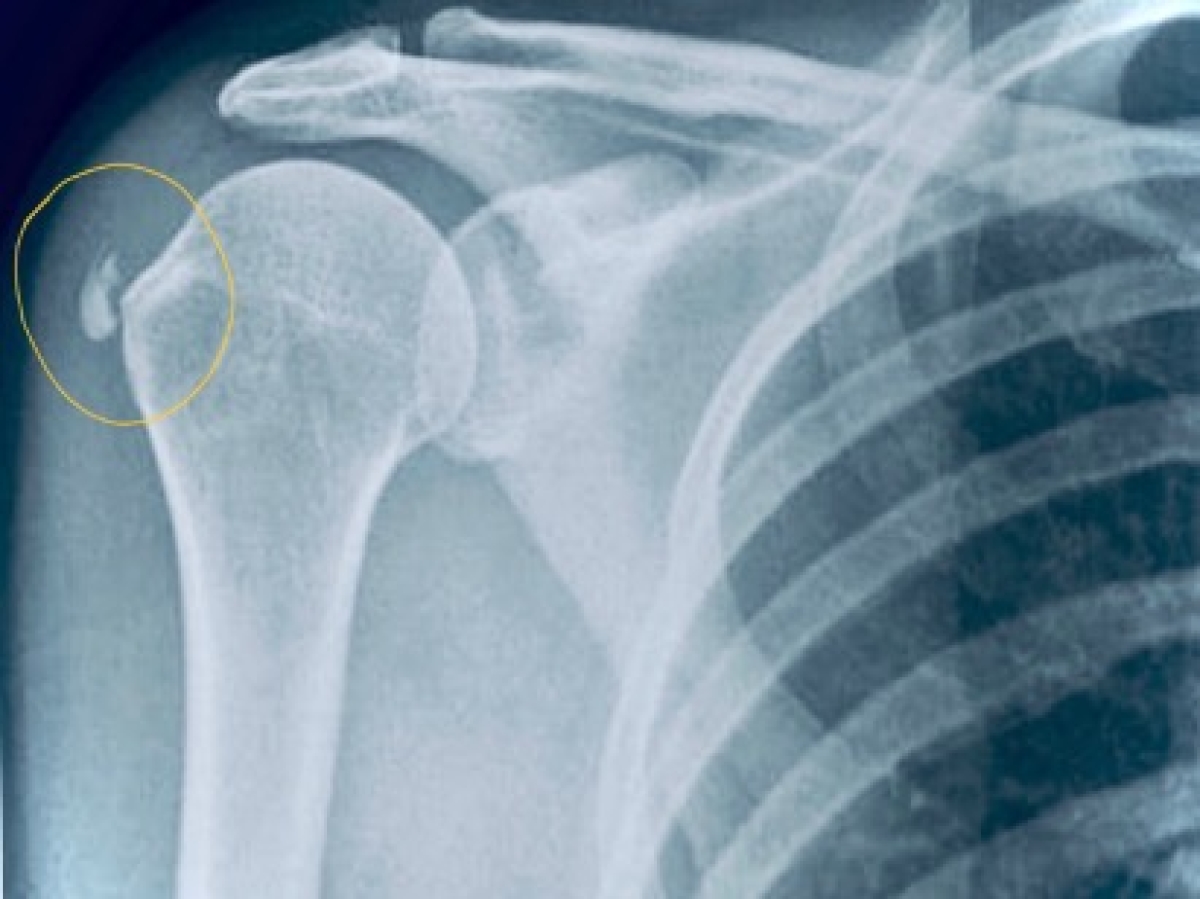

Η ασβεστοποιός τενοντίτιδα του ώμου αφορά φλεγμονώδη εξεργασία της περιοχής του ώμου λόγω εναποθέσεων κρυστάλλων υδροξυαπατίτη στην καταφυτική μοίρα του στροφικού πετάλου. Η περιοχή εναπόθεσης των κρυστάλλων γίνεται στην περιοχή «κρίσιμης Ζώνης», περί το 1-1,5 εκ. από την κατάφυση των τενόντων στο Μείζον Βραχιόνιο Όγκωμα. Η περιοχή αυτή είναι περιορισμένης αιμάτωσης και μπορεί μετά από επαναλαμβανόμενες φλεγμονές να οδηγήσει σε…